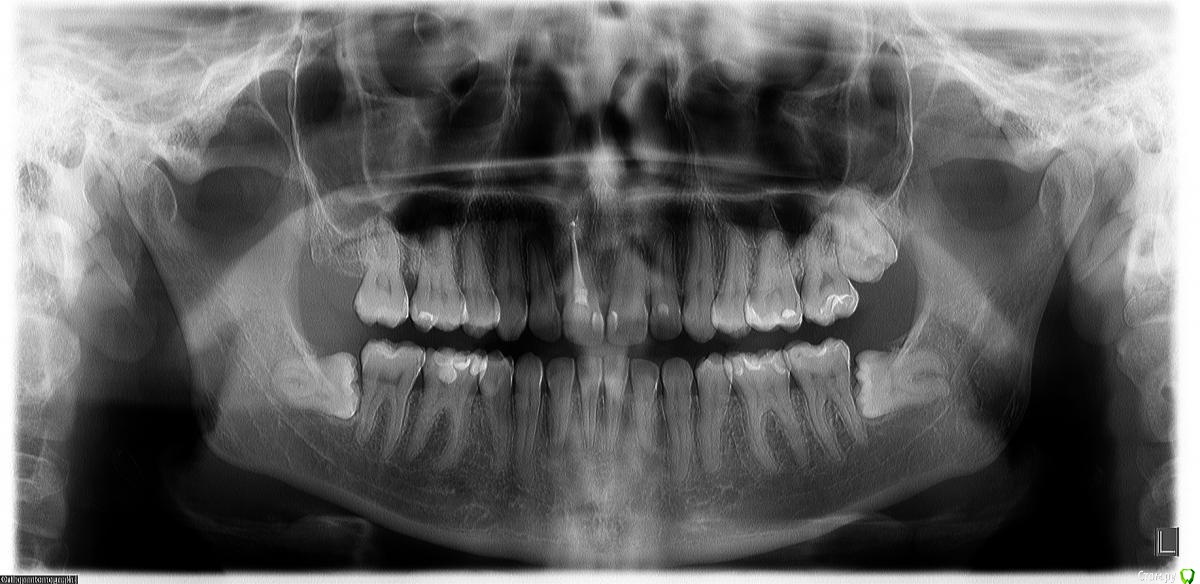

Frisketenner Опубликовано 30 марта, 2016 Поделиться Опубликовано 30 марта, 2016 Добрый день!Лечили 26й зуб (глубокий кариес), сегодня иду к врачу - нужно еще вылечить рядом стоящий зуб, но на пятый день после лечения появились ноющие боли с левой стороны, иррадиирующие то в верхнюю челюcть, то в нижнюю.. Есть предположение, что это может быть внчс, так как ночью боли не беспокоят. Но сегодня сделала панорамный снимок - смотрю, что восьмерка с этой стороны совсем прижимается к 27му зубу. Не может ли это быть причиной появившихся болей?Снимок прилагаю. Заранее спасибо! Ссылка на комментарий

red_butler Опубликовано 30 марта, 2016 Поделиться Опубликовано 30 марта, 2016 необходимо исключить пульпит в зубах слева. А мудрые зубы так и так удалять. 1 Ссылка на комментарий